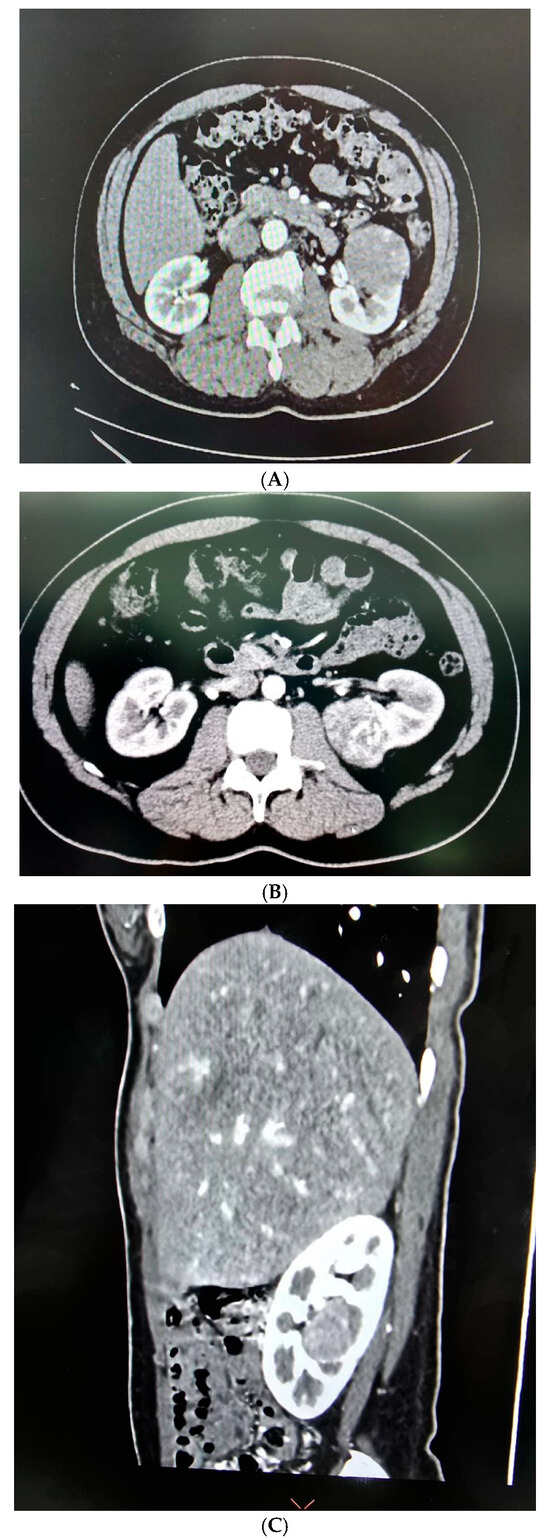

- Retroperitoneal Approach: Patients were positioned in a 90-degree lateral position, and port sites were marked according to the selected approach. A balloon dissector was used to create retroperitoneal space, and trocars were placed at 6 cm intervals using finger guidance or direct vision. Docking of the Da Vinci robotic system was then performed to provide an ideal working space to allow for the robotic arms and camera to obtain accurate surgical access. The bipolar grasper, monopolar scissors, ProGrasp forceps, and a large needle driver were the robotic instruments used for this procedure. The retroperitoneal fat was mobilized, and the lateral coronal fascia was incised. The perirenal fat was then carefully dissected to expose the kidney tumour. The renal hilum was accessed directly, allowing for precise isolation of the renal artery, which was clamped as needed to control blood flow (Figure 2A,B). The tumour was meticulously excised, and the renal defect was repaired in layers using barbed sutures to achieve haemostasis and reconstruct the parenchyma, following the same principles as the transperitoneal approach [19].